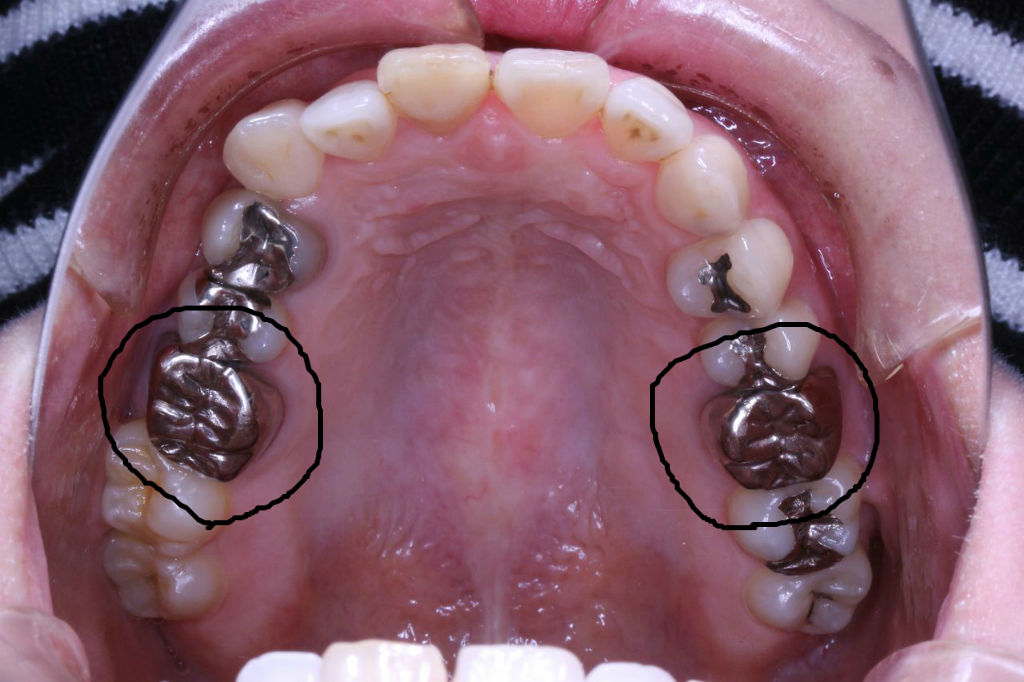

その患者さんの数年前の画像です

現在は他のクリニックで歯列矯正を一切しない方法で治療を開始しており、かみ合わせがおかしくうまくいっていないような気がするとのことでコメントを求めての来院でした。

もともとは

上の歯列はどうでしょうか?